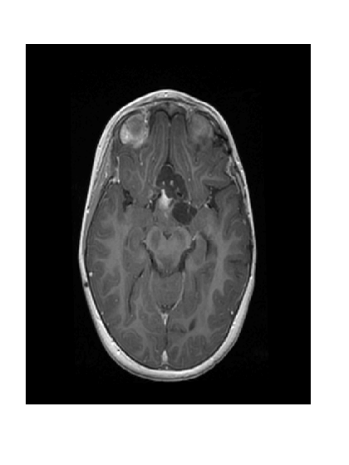

Due to its wide use in image processing, we consider the use of gradient sparsification with LACS-MRI. We show below that it is possible to produce image reconstructions with significantly higher Reconstruction SNR using gradient sparsification. We have repeated some of the simulations from above for different compression levels, , using the gradient transform to sparsify instead of the wavelet transform. We will refer to this as ”LACS-MRI with gradient sparsity.” We compared the performance of each sparsification method at each compression level using LACS-MRI and then compared this to the L1-W method. Again, we use a reference image and a follow-up image that we hope to recover as in Figure 8. We consider here only the phantom image, as it serves as a prime candidate for gradient sparsification, and is small enough that evaluation of all PDFs is computationally feasible.

Figure 12 shows the effect of a 2-fold scale difference on LACS-MRI image reconstructions. There are extensive streaking artifacts and significant detail is lost compared to the ground truth and the reconstruction using the modified method. Clearly, the Grayscale Compensation for Reference Based MRI Algorithm (GSC) can reduce these artifacts and help improve the visibility of structure.